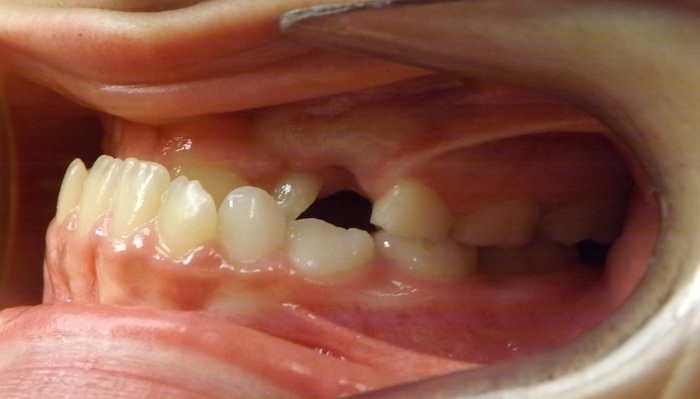

EMILY’S SMILE JOURNEY

Emily began with us as a Phase I patient and we just recently debanded her from Phase II. These progression photos show you that starting early allows us to not just straighten the teeth, but also change the patient’s jaw shape. Emily was a dedicated patient and did great with treatment. Her results speak volumes! We were able to correct her severe underbite and Class III skeletal imbalance without needing jaw surgery.